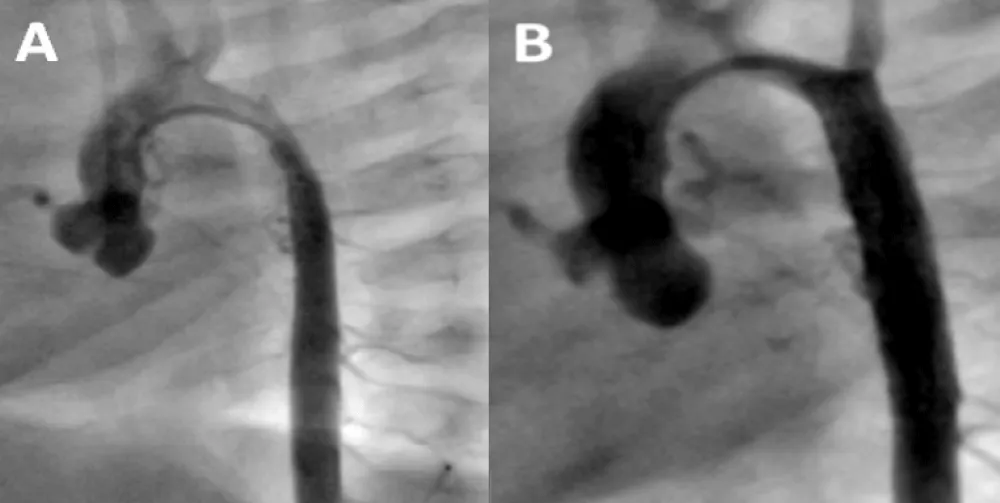

The patient was discharged on aspirin and enalapril and throughout the follow-up persisted growth failure with episodes of bronchial hyper reactivity and reduced femoral pulses with brachial arterial pressure of 130/80 mmHg. Doppler echocardiography a year later confirmed new recoarctation. Balloon angioplasty (BA) of the stent was performed 2 months later after several postponements due to bronchial hyper reactivity. In this procedure (Figure 3A and B, Table 1), the aortogram showed a long in-stent severe irregular stenosis secondary to intimal growth beginning after the origin of the left sub-clavian artery which had ostial involvement, not present in the initial angioplasty, extending up to the distal end of the stent. The stent was dilated successfully with a 3F 8 x 20 mm balloon catheter. However, the aortic lumen did not reach the wall of the stent because of intimal and medial aortic layer thickening. There was no aortic wall damage and there was again a marked gradient decrease through the coarctation.

Figure 3: Balloon Angioplasty for Recurrent Coarctation at age 21 months. A: Diffuse narrowing of the mid aorta with severe intimal proliferation (between arrows); B: Recovery of the aortic lumen post balloon angioplasty.